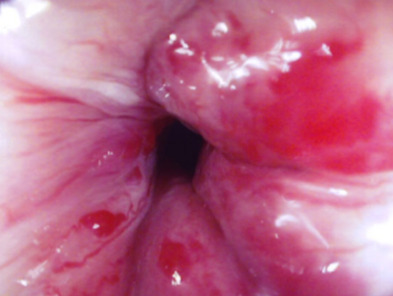

Les hémorroïdes peuvent se manifester de plusieurs façons : par des saignements, par une sensation de boule/gêne au niveau de l’anus et par des douleurs anales à type de cuisson.

Un prolapsus rectal est une extériorisation de la muqueuse rectale à travers l’anus. Il peut entraîner une sensation de gêne au niveau de l’anus de façon intermittente ainsi que des saignements et une incontinence anale.